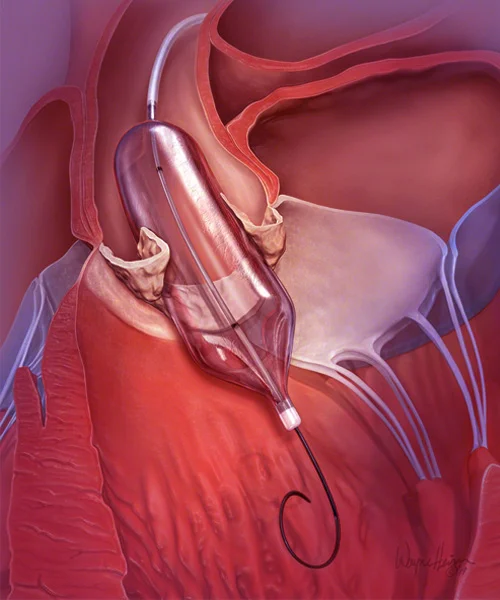

He holds prestigious qualifications including MBBS, MD in General Medicine, and DM in Cardiology, making him a highly skilled expert in interventional cardiology. Dr. Yogesh Nagendra has extensive expertise in procedures such as angiography, angioplasty, pacemaker implantation, Balloon Mitral Valvotomy (BMV), ECHO, and TMT, ensuring accurate diagnosis and effective treatment for every patient.